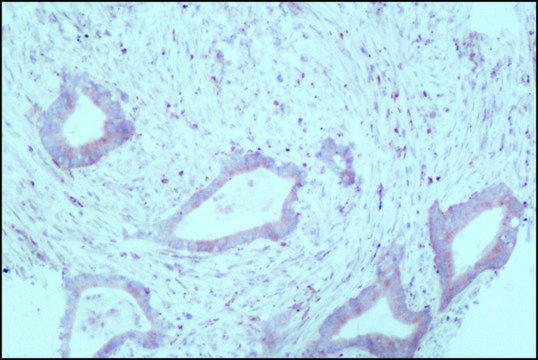

immunohistochemistry: suitable

Monoclonal Anti-Tryptophan Hydroxylase (mouse IgG3 isotype) is derived from the WH-3 hybridoma produced by the fusion of mouse myeloma cells and splenocytes from BALB/c mice. Tryptophan hydroxylase (TPH; L-tryptophan tetrahydropteridine:oxygen oxidoreductase; EC 1.14.16.4), the rate-limiting enzyme for the synthesis of serotonin, is a very specific enzyme found only inside serotoninergic neurons.

The tryptophan hydroxylase 1 gene (TPH1) is a 444 amino acid protein encoded by the gene spanning 29 kbp with11 exons on human chromosome 11p15.3-p14. The enzyme is expressed in the gut, spleen, thymus, pituitary and also in the pineal gland.

Monoclonal Anti-Tryptophan Hydroxylase antibody produced in mouse has been used in:

• immunohistochemistry